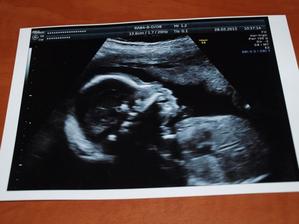

Druhé děťátko

stále nepřichází, ale my věříme, že už to dlouho nebude trvat a přijde mezi nás. těší se na něj Maminka, Tatínek a Bratříček Martínek